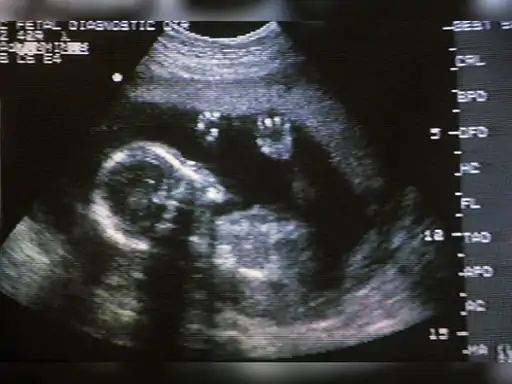

कार्रवाई के दौरान डिकोय गर्भवती महिला को पहले कुबेर हेल्थ केयर बुलाया गया, जहाँ उससे 80 हजार रुपए की डील हुई। इसके बाद आरोपियों ने उसे कई रास्तों से घुमाते हुए मयूर रेजिडेंसी के एक सुरक्षित फ्लैट पर ले जाकर सोनोग्राफी की और गर्भ में लड़की होना बताया। इशारा मिलते ही एएसपी डॉ. हेमंत जाखड़ और सीआई सत्यपाल यादव के नेतृत्व वाली टीम ने दबिश देकर आरोपियों को रंगे हाथों दबोच लिया। राजस्थान में गिरते लिंगानुपात के बीच इस तरह के गिरोह का सक्रिय होना बेहद चिंताजनक है, जहाँ वर्तमान में 1000 लड़कों पर करीब 890 बेटियां ही दर्ज की जा रही हैं।